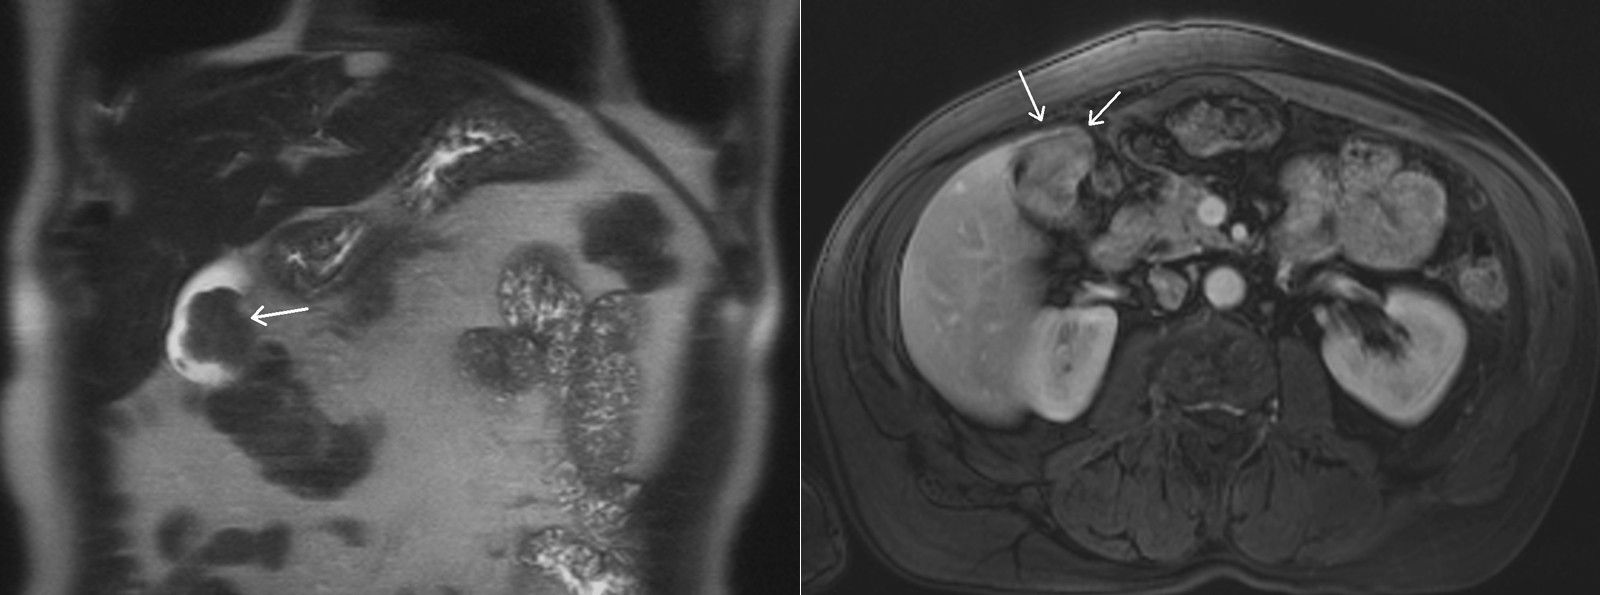

A 60-year-old woman presents with vague abdominal pain in the right upper quadrant. An ultrasound reveals a gallbladder abnormality. Abdomen magnetic resonance imaging (MRI) from this patient is shown below (coronal T2-weighted and axial postcontrast T1-weighted), with the abnormality depicted with arrows.

What is the diagnosis?